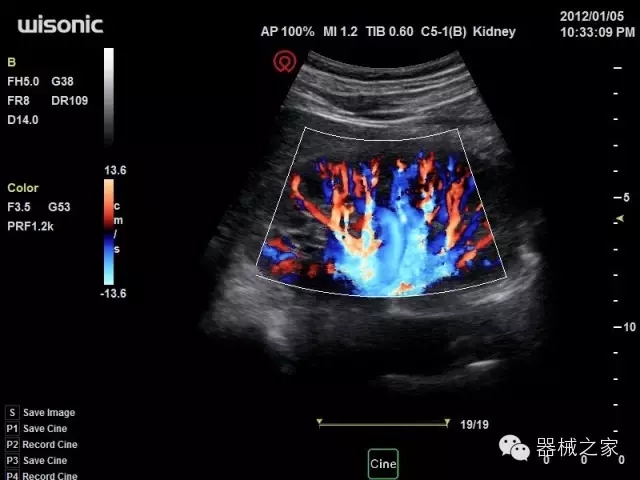

經(jīng)典產(chǎn)品:四葉草

臨床圖片賞析

產(chǎn)品特點(diǎn)

·全球目前唯一一款配備主機(jī)雙探頭接口,整機(jī)重量(含電池)在5公斤以內(nèi)的便攜式彩超;

·一款互聯(lián)網(wǎng)彩超,只要有手機(jī)信號(hào)的地方就可以非常方便地實(shí)現(xiàn)遠(yuǎn)程會(huì)診和病案調(diào)??;

·獨(dú)有的HoloTM PW 實(shí)時(shí)3取樣門PW成像技術(shù),精確進(jìn)行血管診斷;